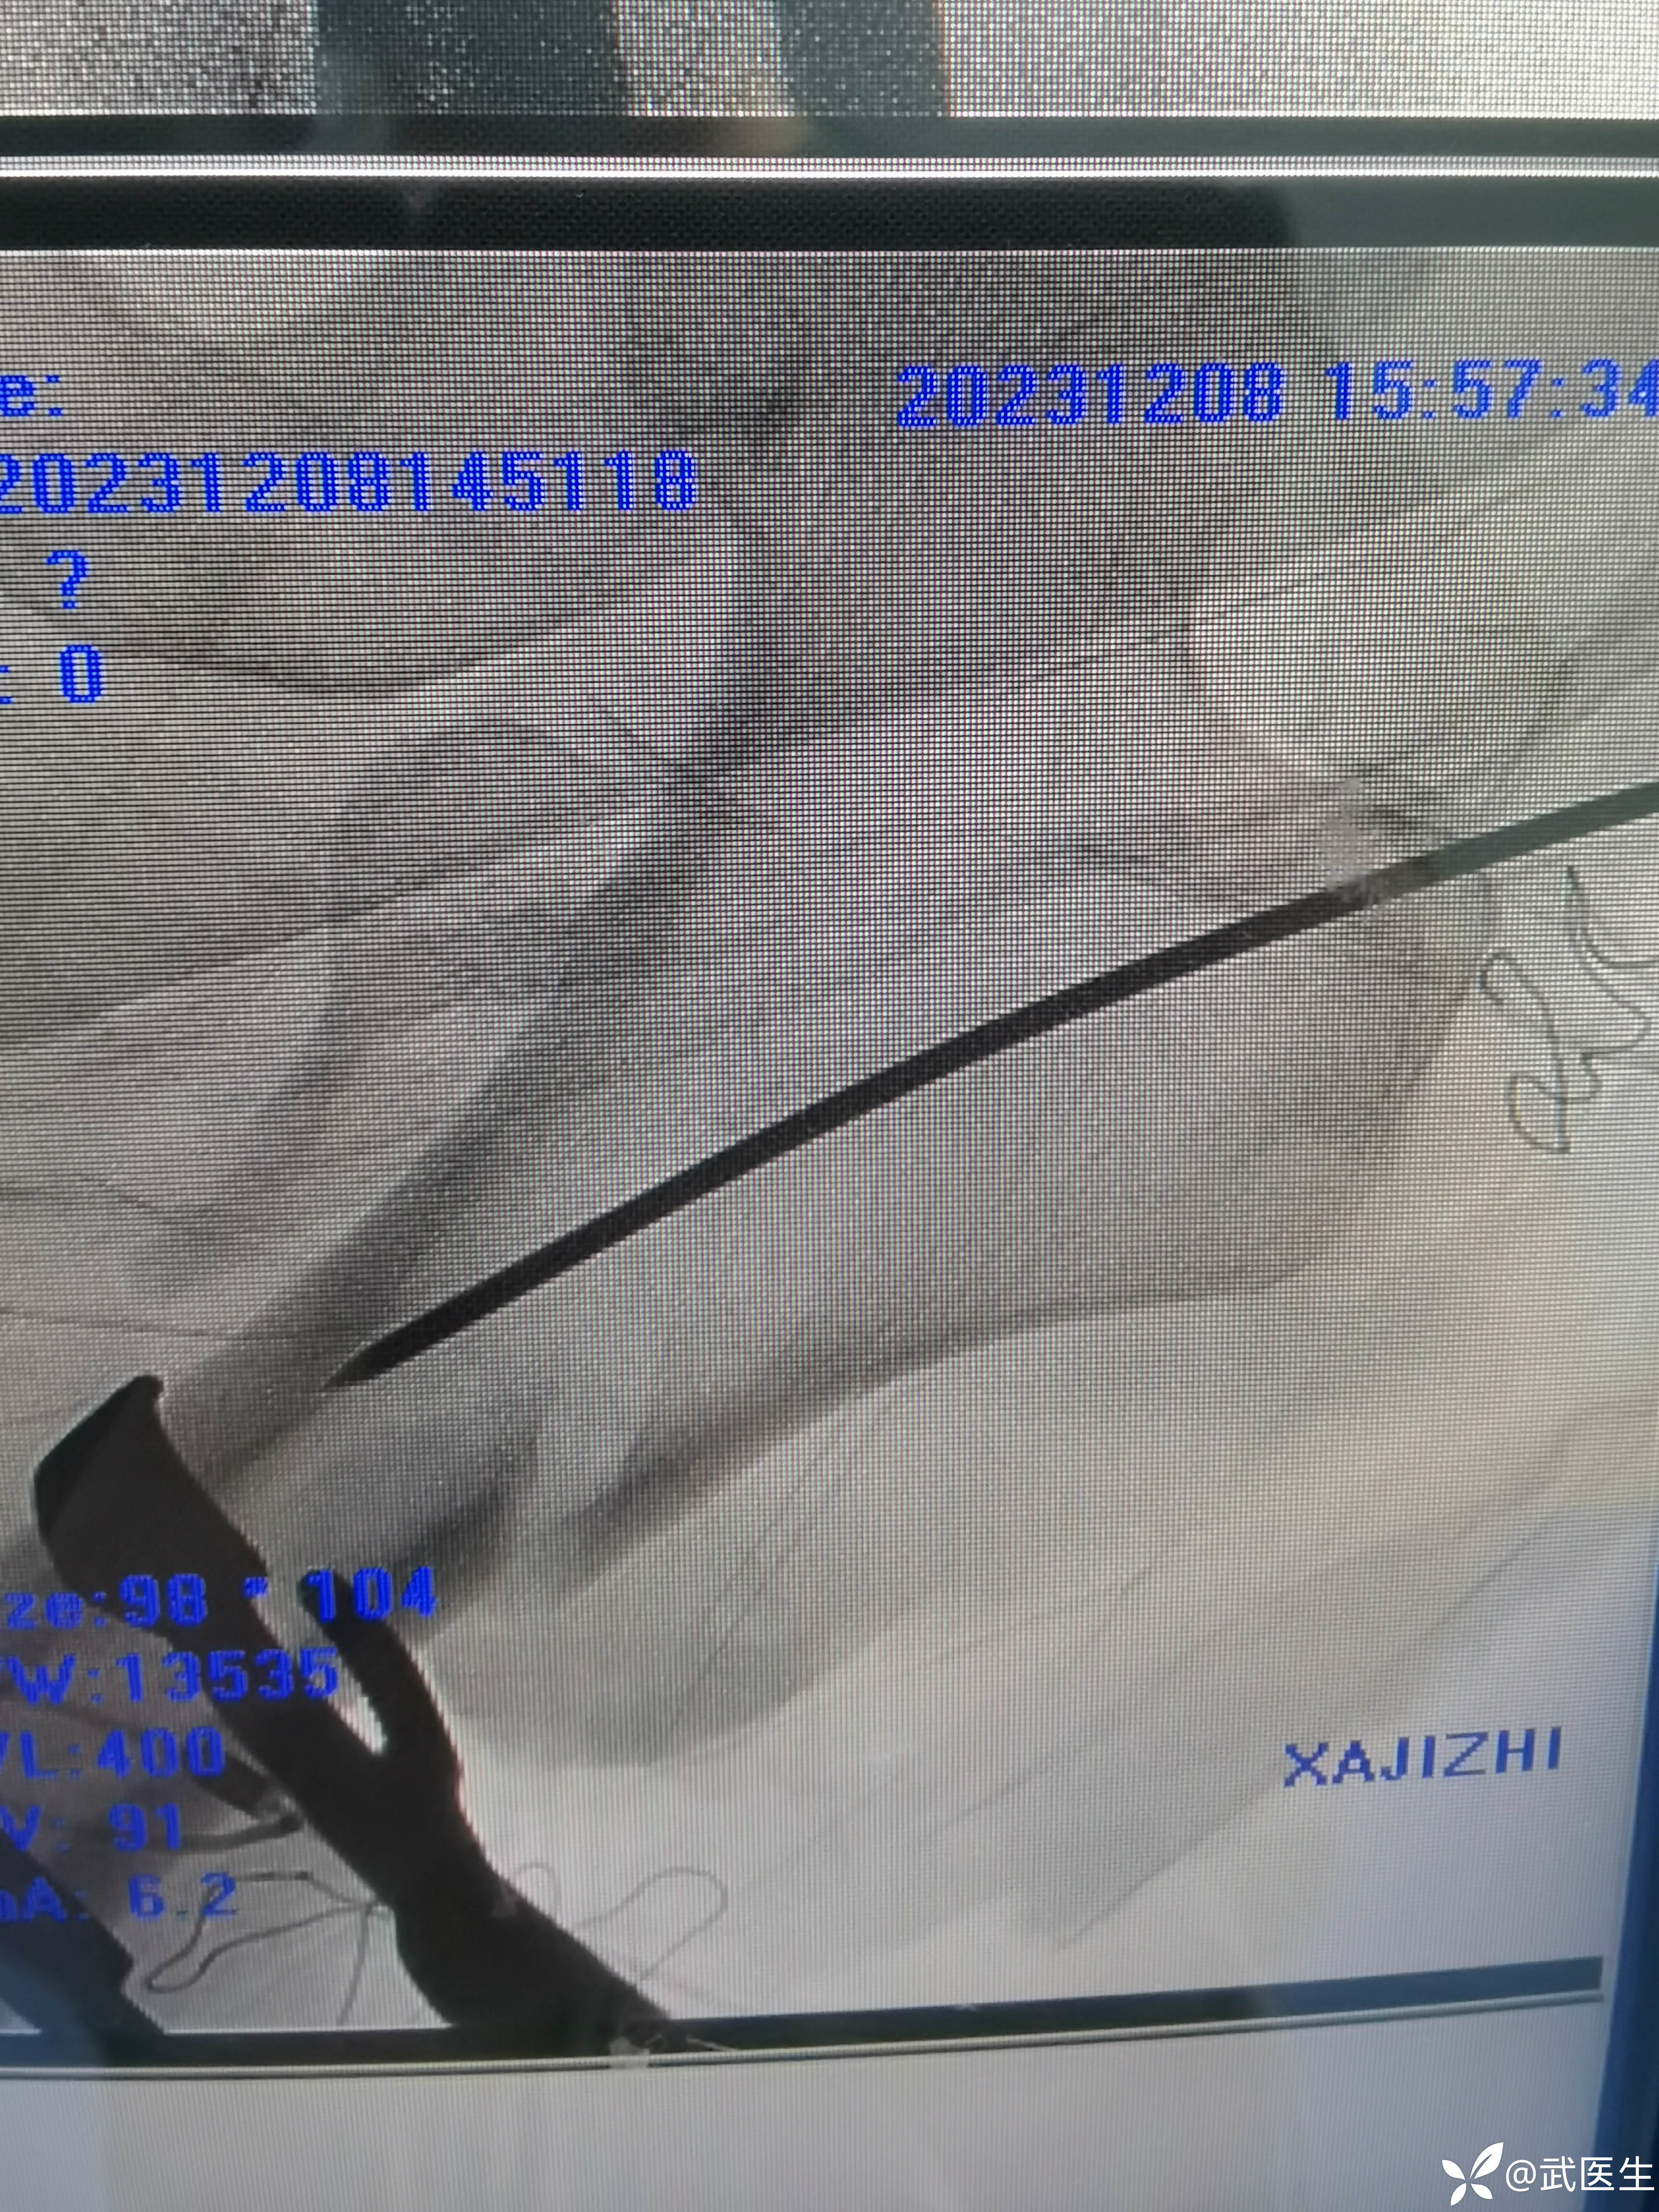

C臂透视如下,果然和书上一样

直接切开持骨器维持复位,钛缆初步固定

定位